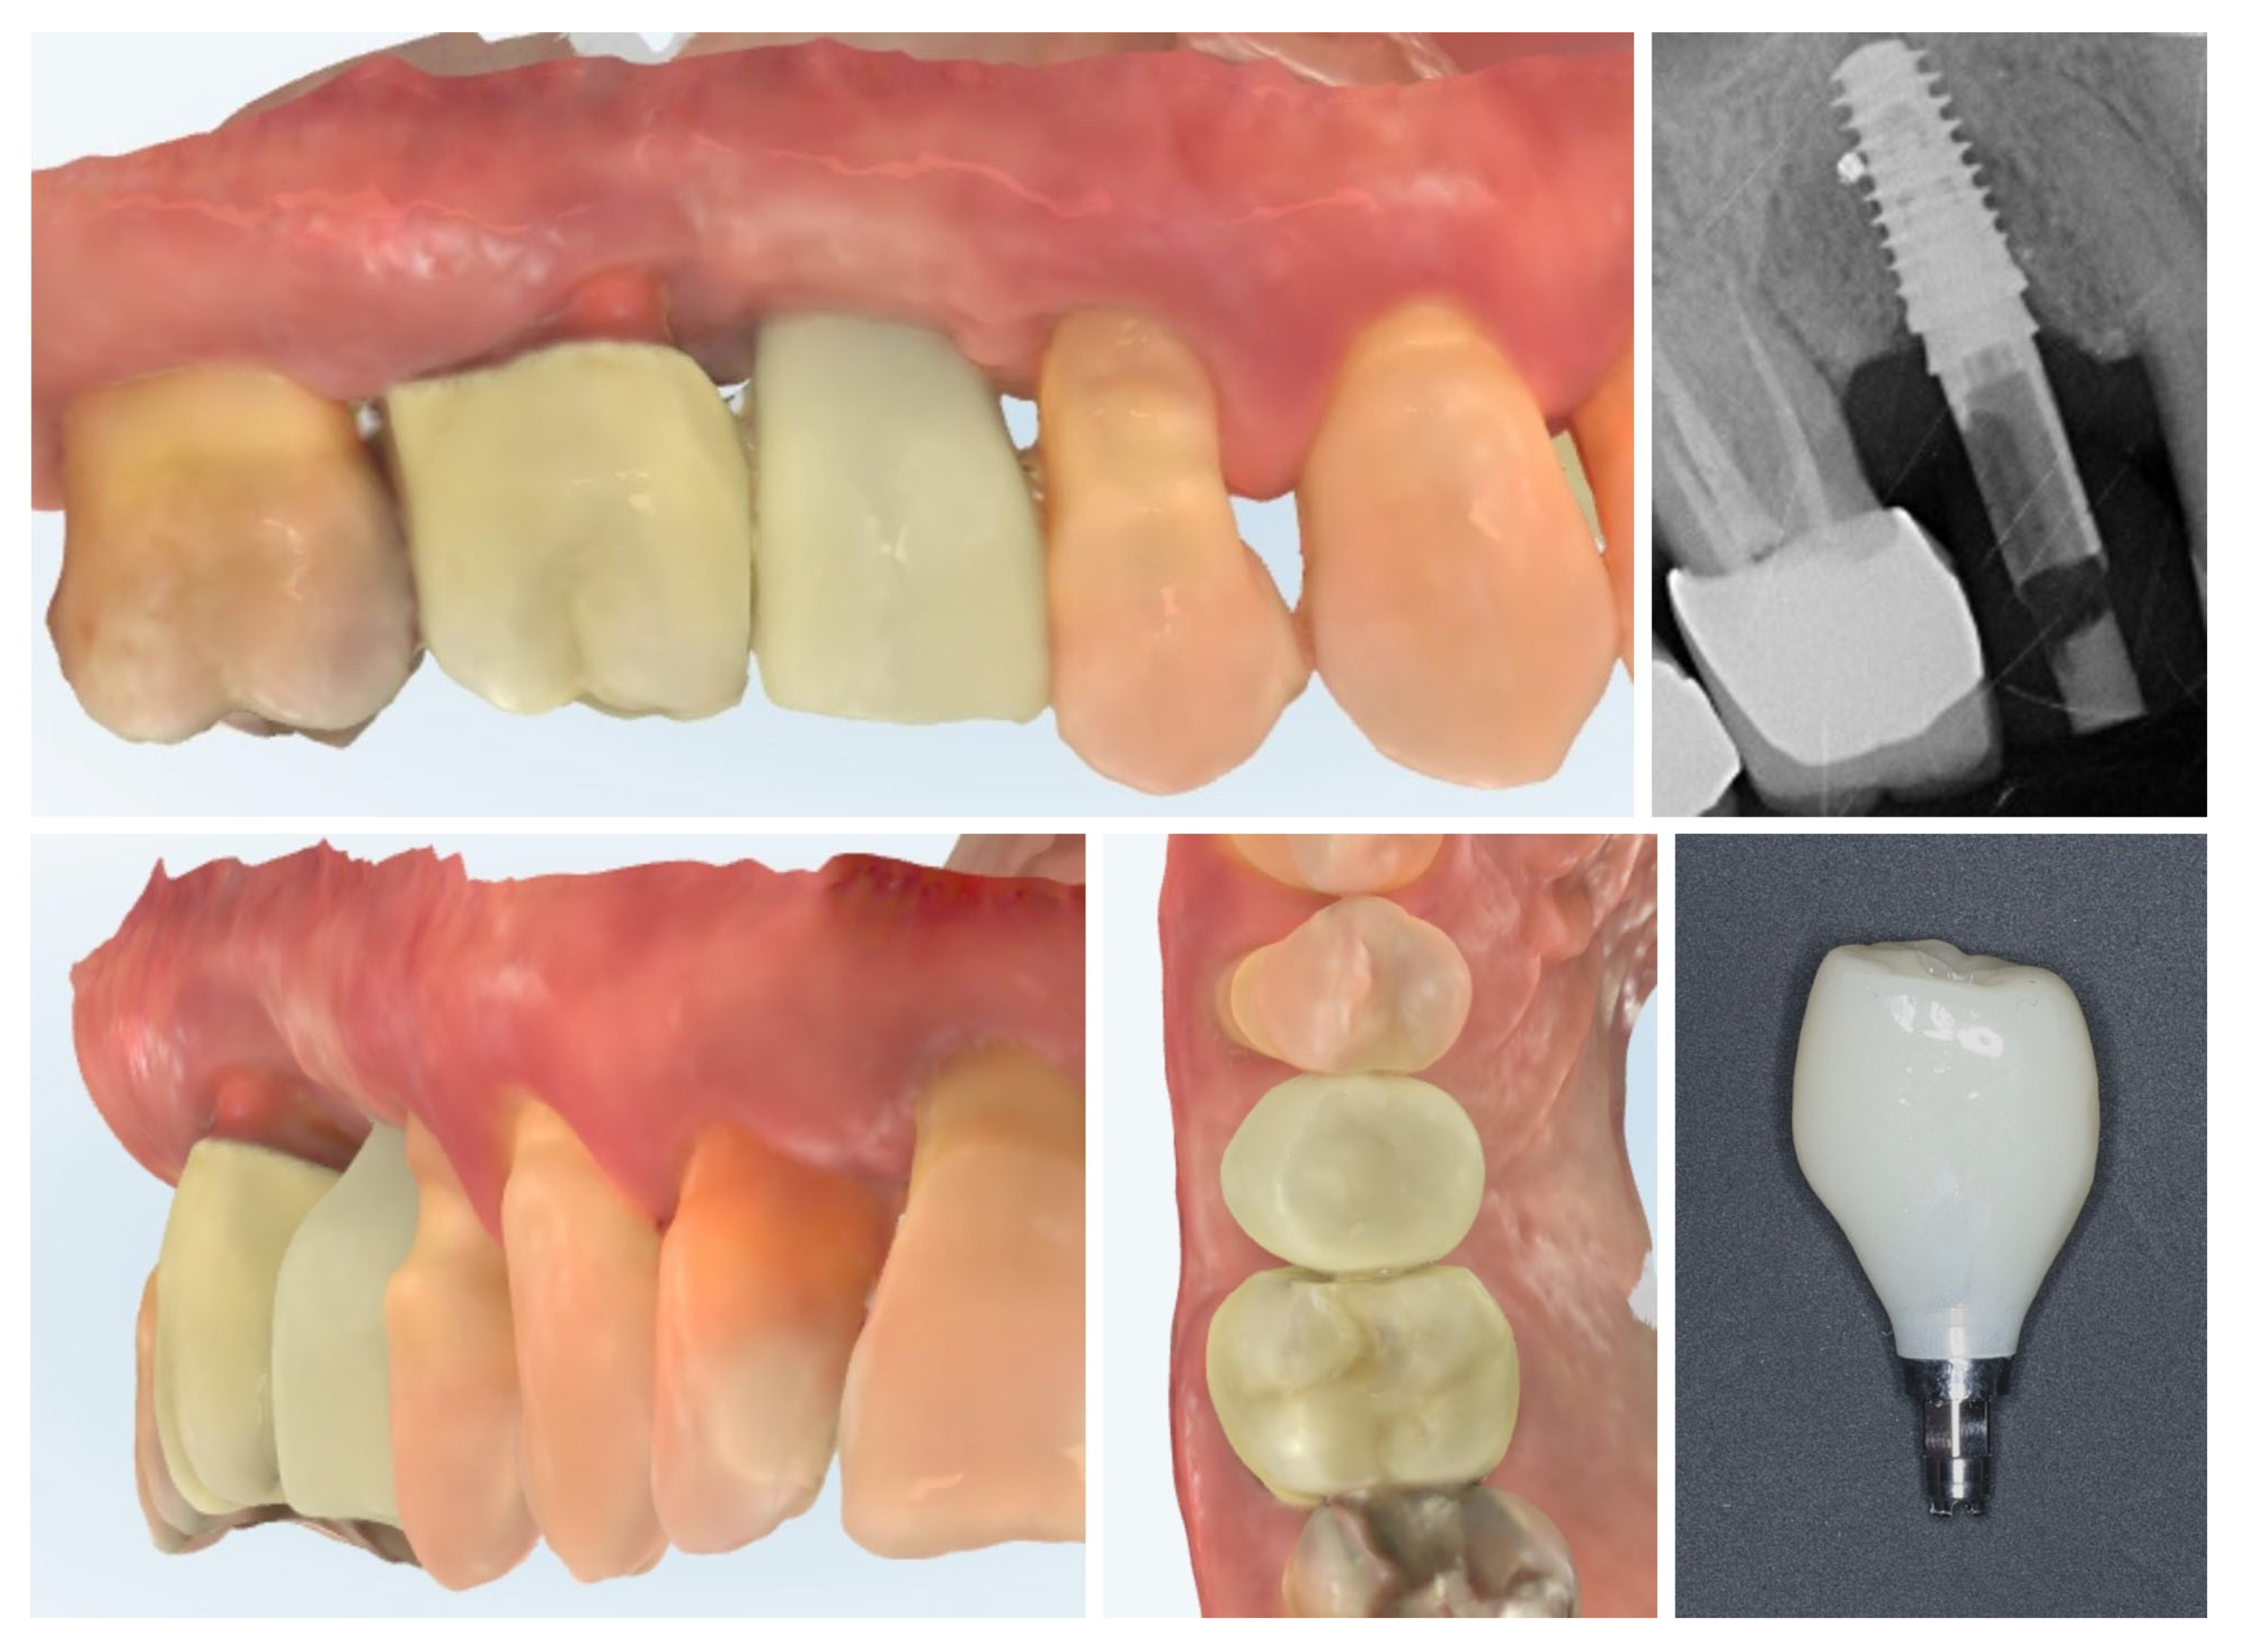

2. Materials and Methods—Clinical Case

| 3 | 3 months post-op (with provisional) | 3.4 | 3.4 | Increased thickness, stable bone and mucosa |

| 4 | 4 months post-provisional | 3.5 | 3.6 | Stable peri-implant mucosa around provisional crown |

| 5 | 8 months post-op (final crown) | 3.5 | 4.1 | Final crown placed, harmonious soft tissue contours, and stable crestal bone |